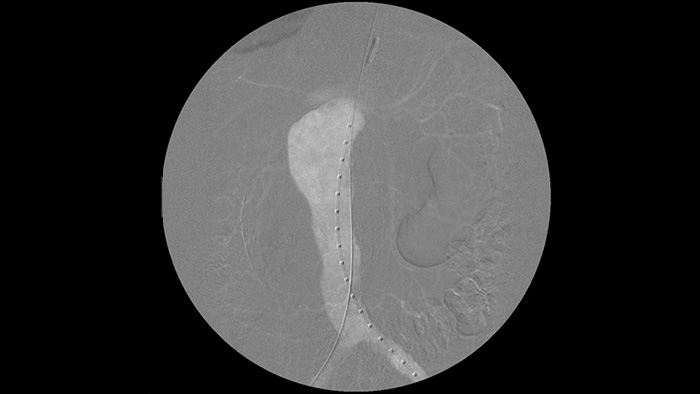

La angiografía por sustracción digital (ASD) se utiliza en procedimientos vasculares intervencionistas para ver con claridad los vasos sanguíneos mediante la eliminación de estructuras que pueden oscurecer la visibilidad de los vasos. La hoja de ruta de fluoroscopia superpone la imagen de contraste sustraída con anterioridad adquirida en la fluoroscopia en vivo, lo que le permite rastrear el dispositivo sin reinyectar el contraste.

Mejore la visibilidad de la vasculatura tortuosa con opciones de medios de contraste de yodo y CO2. Controle fácilmente las inyecciones desde la mesa. Para los pacientes con insuficiencia renal, puede utilizar la opción de CO2 para ver con facilidad los vasos pequeños sin usar contraste de yodo.